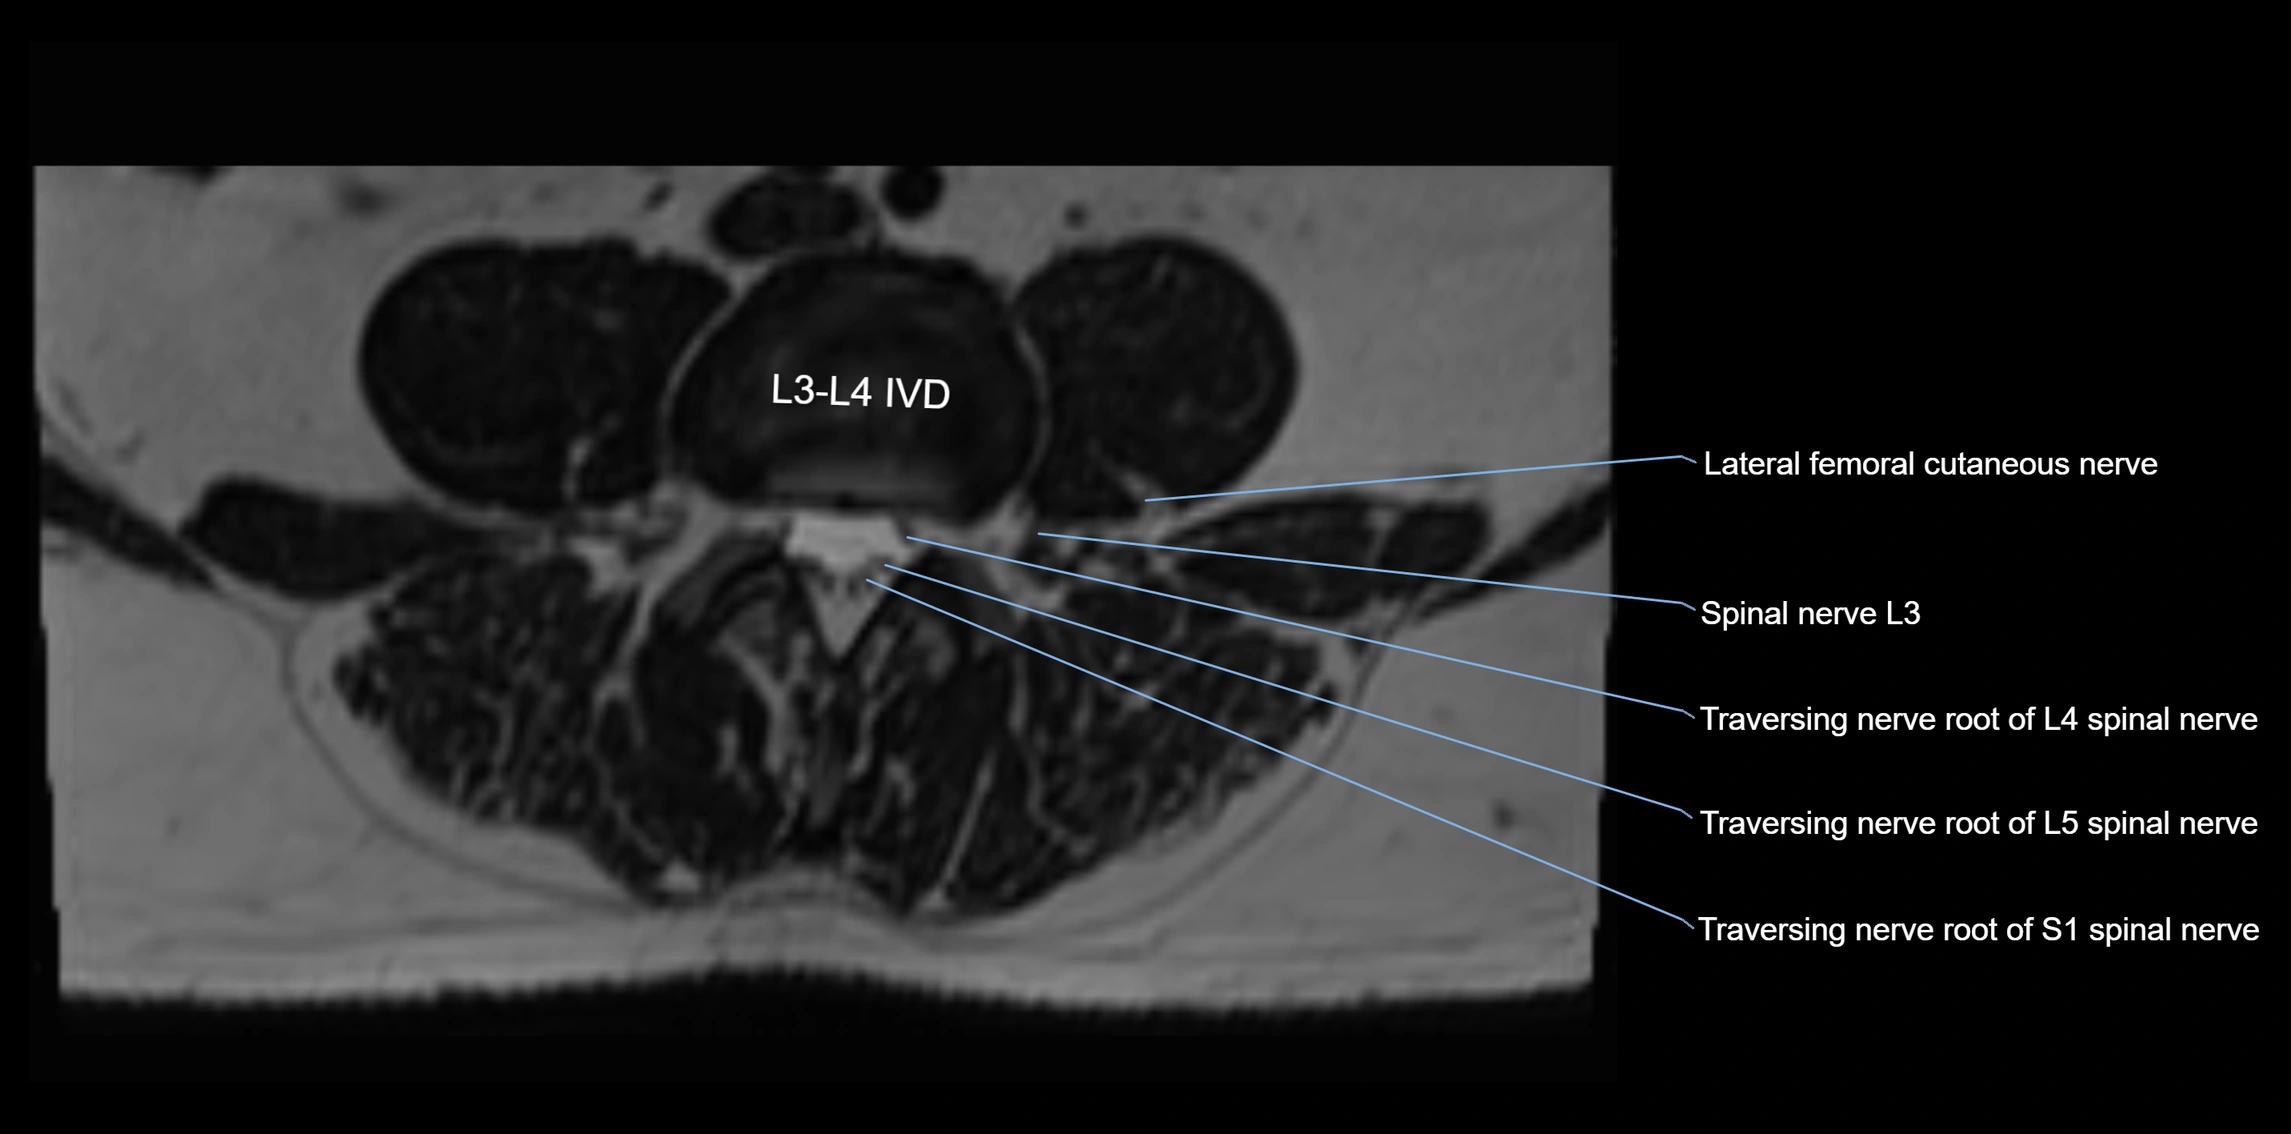

MRI Appearance

T1-weighted images:

• Nerve appears as a very thin low-to-intermediate signal intensity structure

• Surrounded by bright fat, aiding visualization

T2-weighted images:

• Nerve shows intermediate to mildly hyperintense signal compared to muscle

• Pathological involvement appears brighter

3D T2 SPACE / CISS:

• Nerve appears intermediate to mildly hyperintense compared to muscle

• Surrounded by bright fat or CSF, improving visualization

• Best sequence for mapping small pelvic nerves such as the anococcygeal